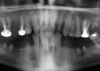

Le panoramique de contrôle à 4 ans montre la parfaite intégration des implants, conséquence de l’hygiène parfaite du patient.